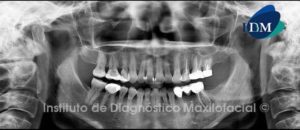

Paciente 61 años de edad, sexo masculino, es referido a la consulta radiológica para la colocación de implantes dentales en el maxilar inferior.